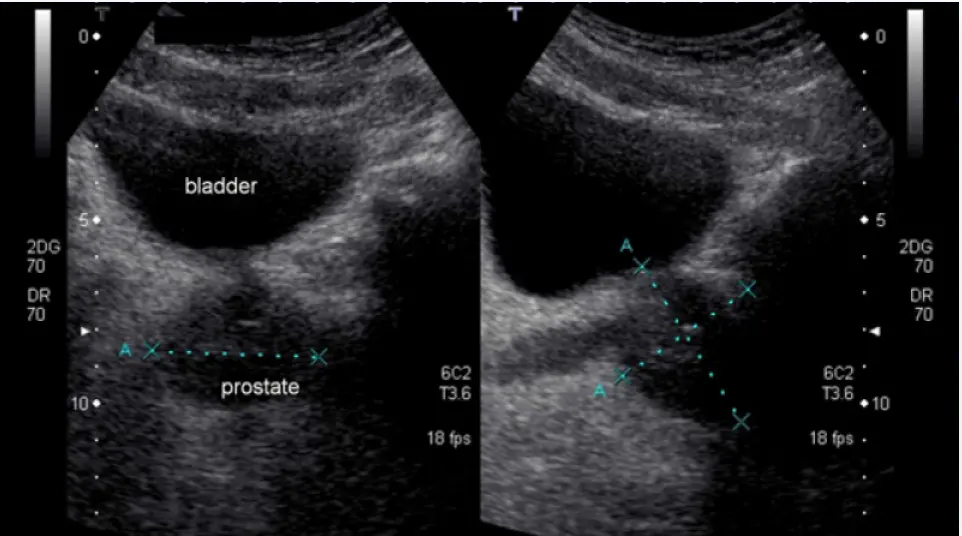

اولا ، التهاب البروستات لدي ليس مزمنًا. اصبت بالبرد أثناء الصيد ، في البداية اعتقدت أنني مصاب بالتهاب في المسالك البولية ، لأنني كثيرًا ما أجري. ثم كان هناك ألم في الفخذ ، وعدم الراحة أثناء التبول . باختصار ، ركضت إلى الطبيب ، قاموا بفحصي وجعلوني سعيدًا ، يقولون ، أنت ، يا صديقي ، مصاب بالتهاب البروستاتا. هنا ، بالطبع ، تومضت حياتي الجنسية بالكامل أمام عيني ، لقد ظننت انه لن استطيع ممارسة الجنس بعد هذا ، لكن الطبيب قال أننا سنتعالج.

كما أوضح لي الطبيب ، Mor prostamin- هذا منتج مصنوع من مواد خام طبيعية. يستخدم هذا المنتج للوقاية والعلاج من التهاب البروستاتا. العلاج يخفف الألم ويزيد من الفاعلية. ليس له نظير في العالم.